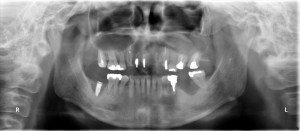

右下7番部位のインプラント埋入後のパノラマです。